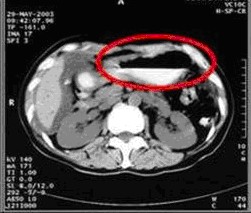

女,49歲。胃體癌晚期,胃竇增厚強(qiáng)化,與周?chē)尺B,腹膜增厚,腹腔廣泛轉(zhuǎn)移,伴大量腹水。放/化療失敗,無(wú)法手術(shù)。治療方案:腹腔灌注今又生2×1012VP/2次/周,共12周,同時(shí)灌注順鉑和5-氟尿嘧啶腹腔,后4周加8次全腹熱療。治療后:第3周,腹水消失;第8周,胃竇、腹膜和網(wǎng)膜變薄,盆腔結(jié)節(jié)明顯變小。后行手術(shù)切除殘余胃腫瘤,術(shù)中探查全腹和盆腔未捫及腫瘤。術(shù)后病檢胃腫瘤內(nèi)未見(jiàn)癌細(xì)胞。

治療前胃竇增厚強(qiáng)化,與周?chē)尘o,腹膜增厚,大量積水